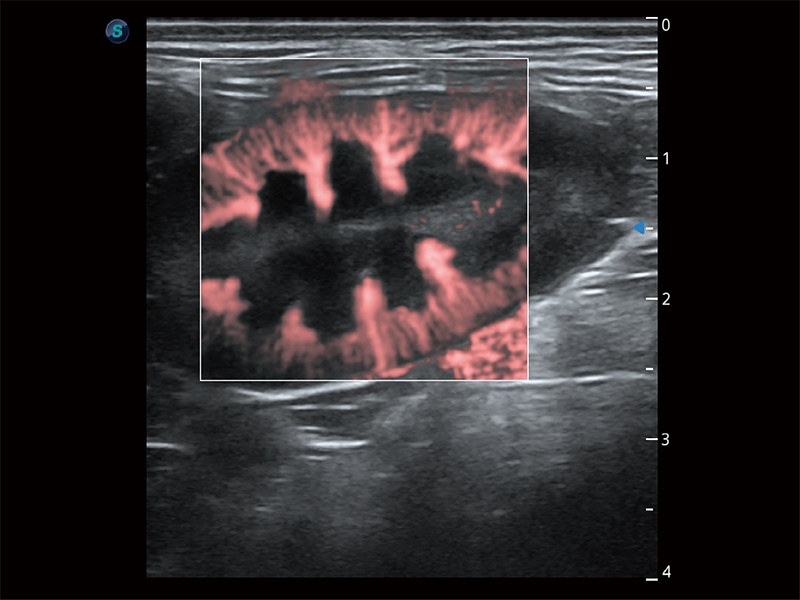

操作简便,无需高频度外力作用即可真实反映组织的形变,快速评估肿瘤良恶性。

非线性融合造影成像充分利用谐波和基波信号,为难以观察的血流进行增强显像。可用于线阵、凸阵、微凸阵、相控阵探头。